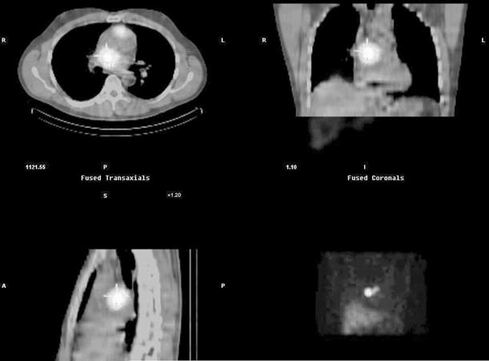

Obr. 2: Snímky SPECT/CT na kterých se zobrazují dvě akumulující ložiska, která jsou uložená prekardiálně a retrokardiálně.

Opětné zvýšení hladin katecholaminů nás vedlo k pokusu o opakování 123I-MIBG vyšetření s výslednou detekcí dvou lézí lokalizovaných před a za srdcem.